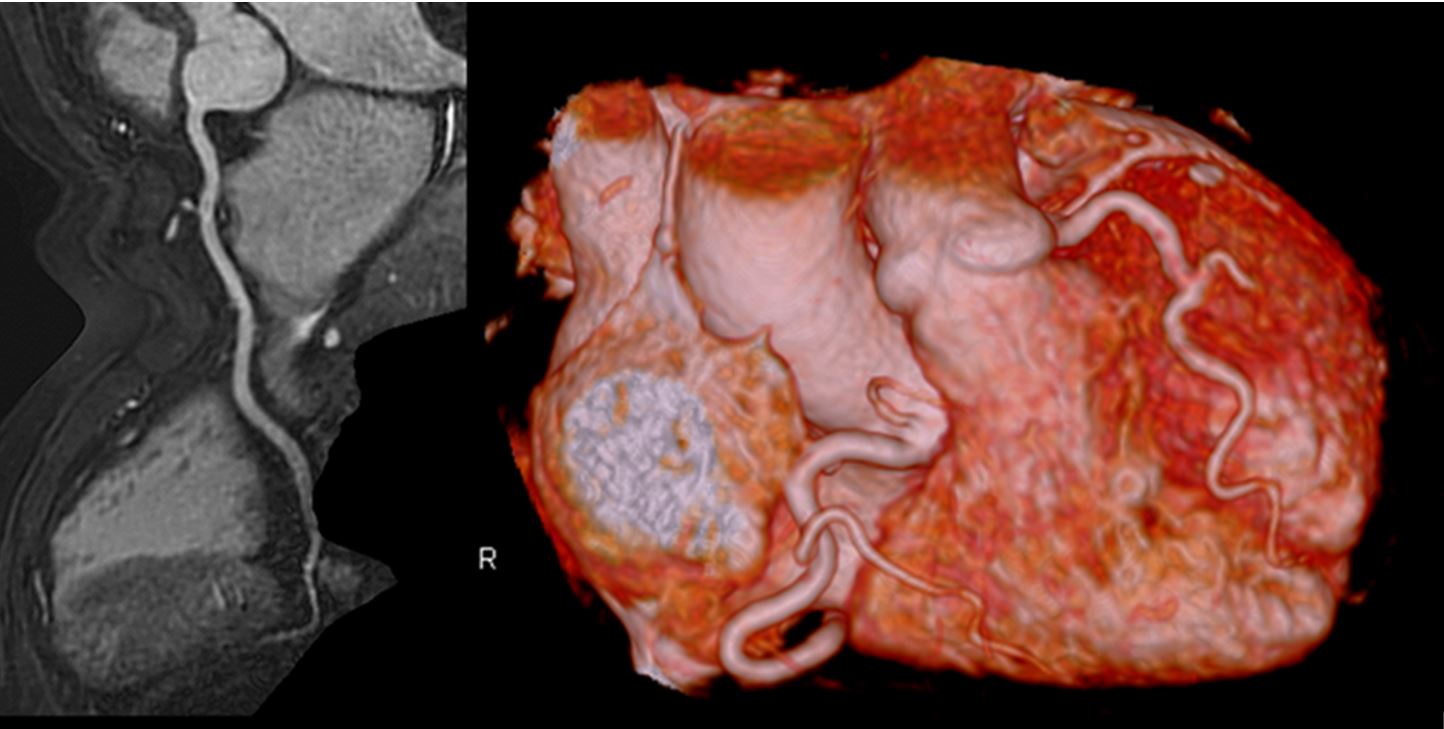

MRI検査室

MRI検査室はフィリップス社製1.5T、3.0T装置2台で検査を行っています。一日約30~40件程の検査を行い、救急患者の検査にも対応しています。いずれの装置もフィリップス社最新アプリケーションを使用することが可能であり1.5T装置でも3.0T装置と同等の画像を得ることが出来ます。それぞれの装置の特徴を活かした高度な検査を行っています。

非造影心臓ドック・冠動脈MRA